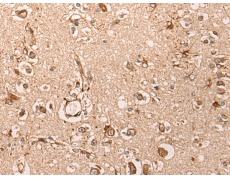

IHC positive control: |

Human lung cancer and human brain |